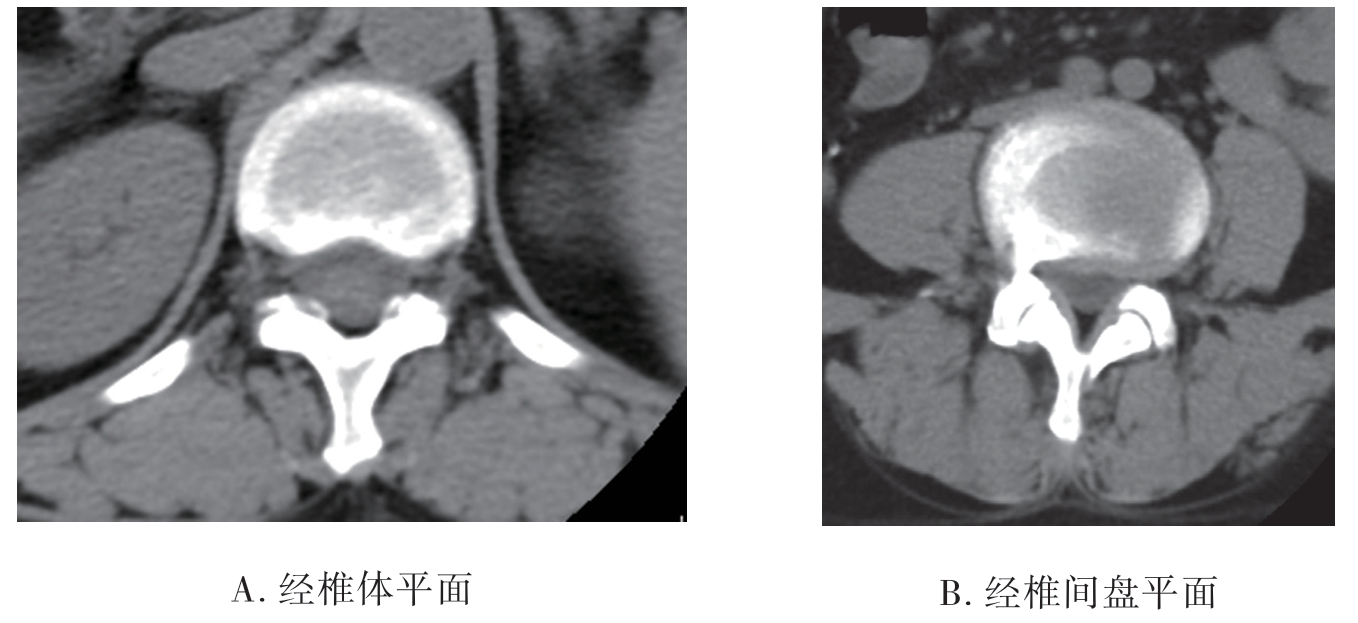

(3)腰椎CT平扫:经椎体平面可见椎体、椎弓根、横突、棘突、椎管(图7-2-7A)。经椎间盘平面可见椎间盘、椎间关节黄韧带等(图7-2-7B)。冠状面可显示椎体、椎间隙、腰大肌等。三维表面重建可显示表面形态、结构及排列。

图7-2-7 腰椎CT平扫